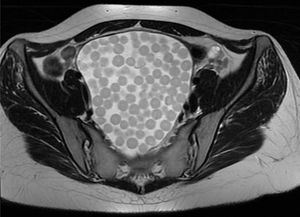

Paciente mujer de 23 años de edad, sin antecedentes conocidos, que consulta por retención aguda de orina recidivante. Se inicia estudio con ecografía abdominal, que se completa con TAC y RMN (figs. 1 y 2) de pelvis. Con hallazgos de teratoma sacrococcígeo de 12cm.

El teratoma quístico maduro es el tumor ovárico más común. Ofrece una imagen típica en RMN llamada en «bolsa de canicas», donde los glóbulos flotantes suelen tener un nido compuesto por detritos, material descamativo o vellos finos que es hiperintenso en T2 e hipointenso en T1.